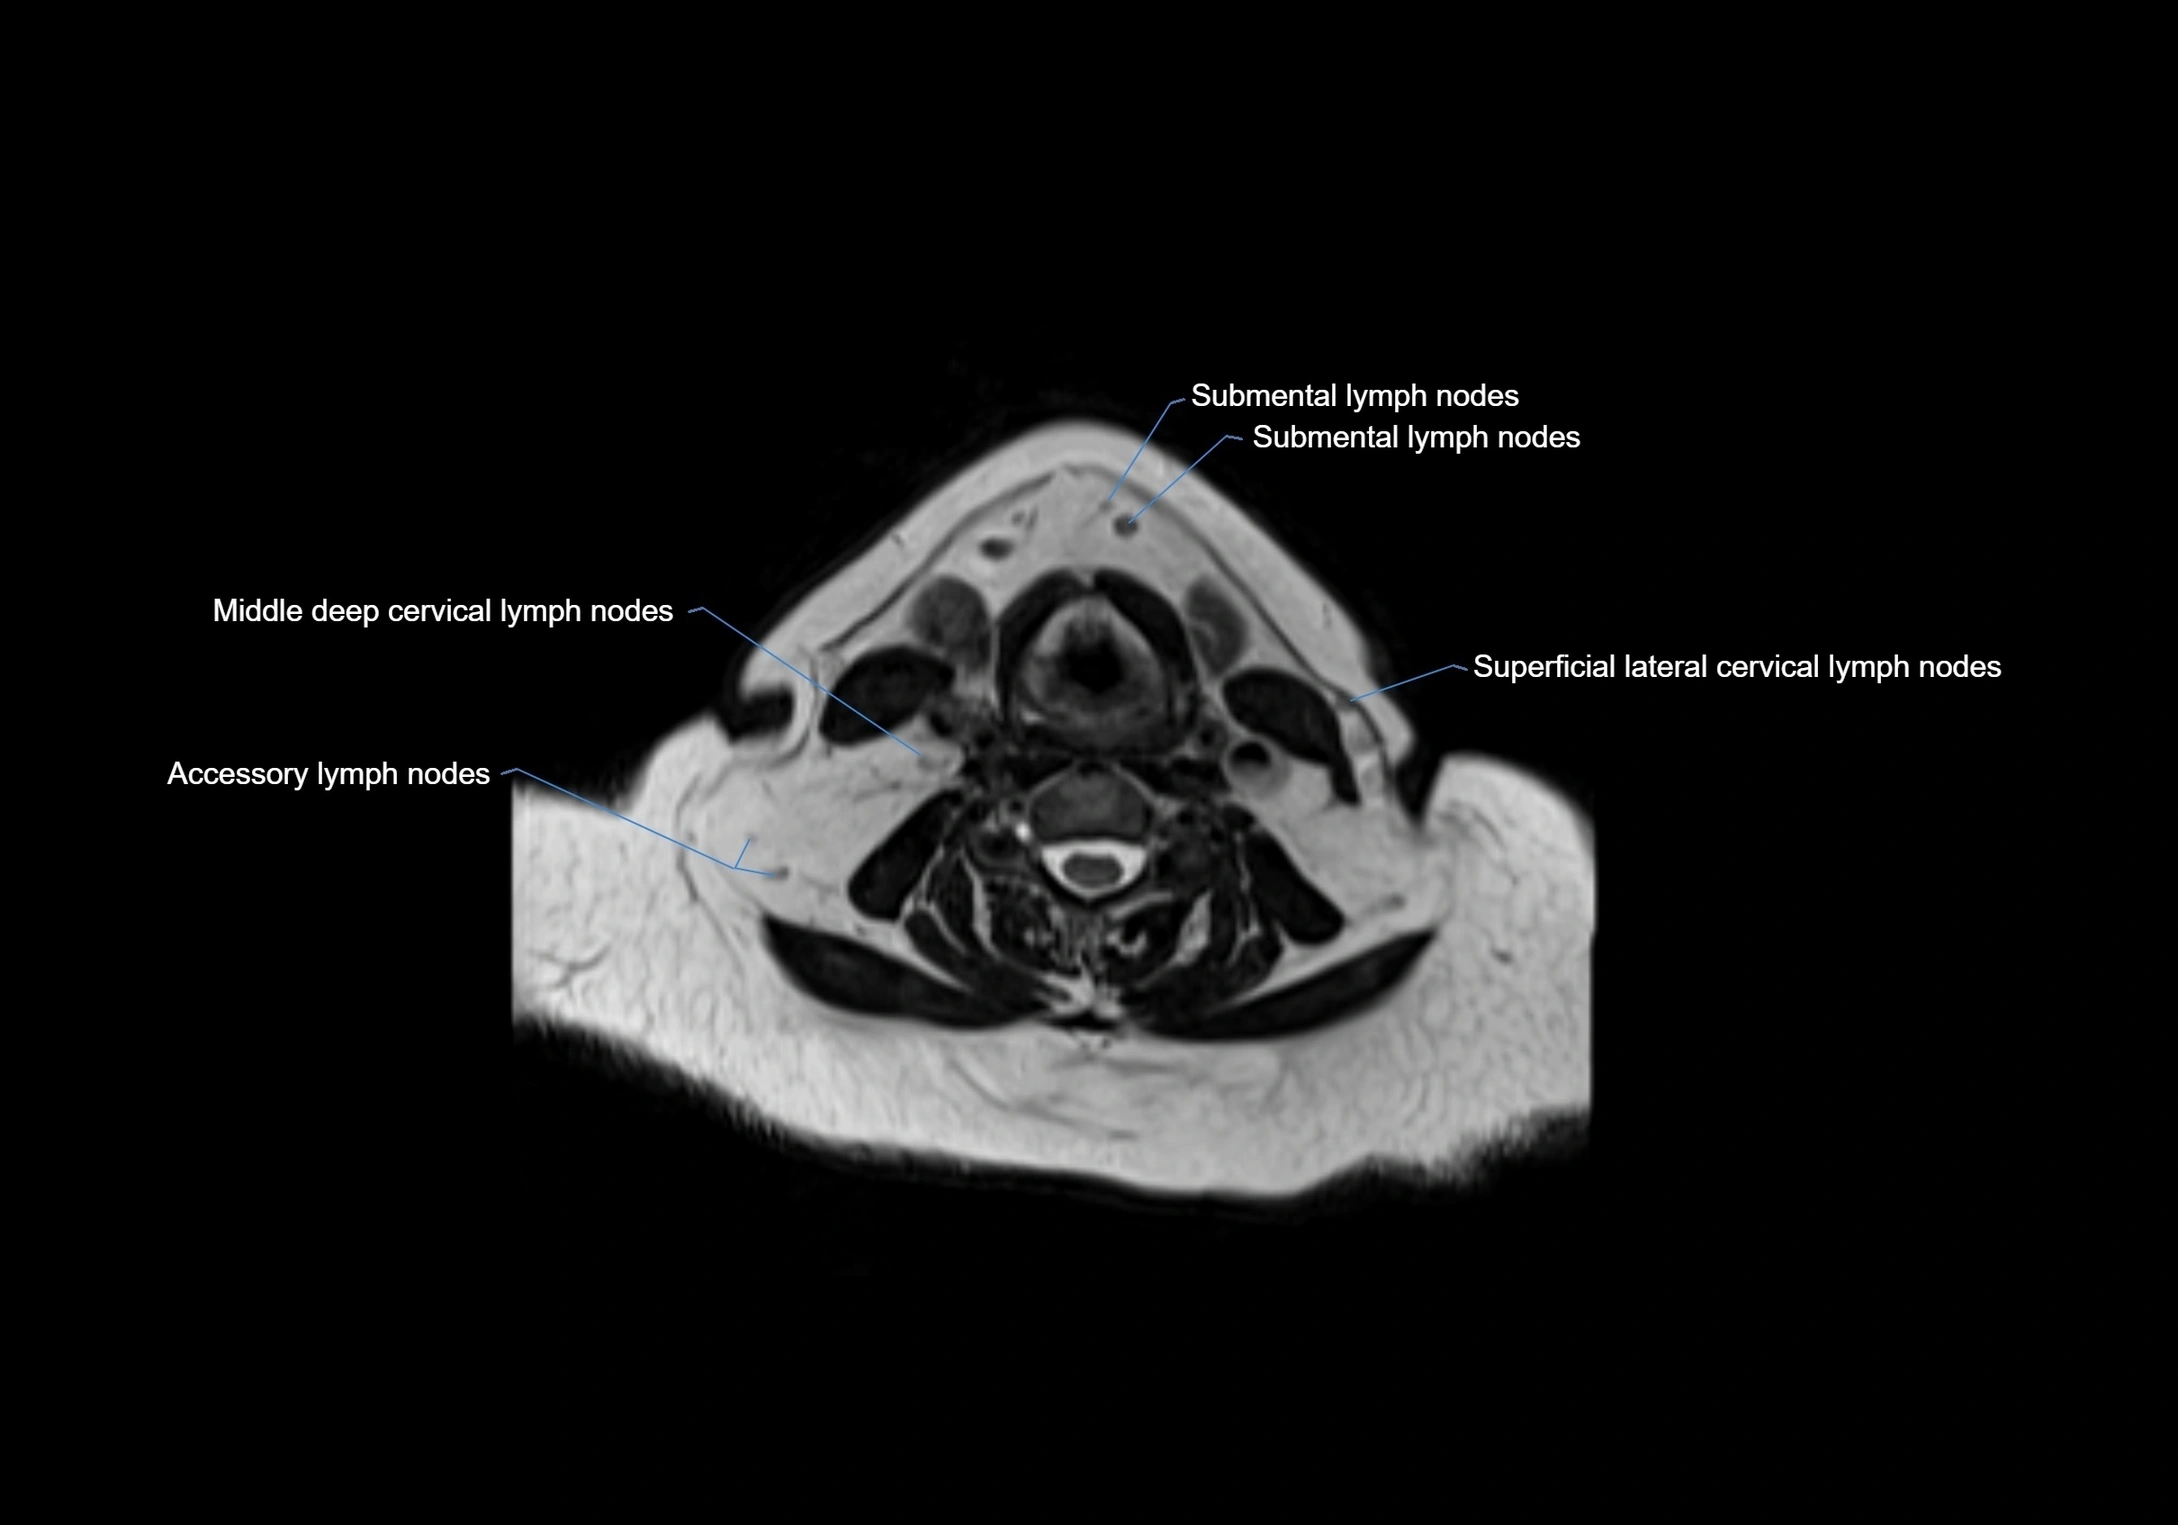

Accessory lymph nodes

Accessory lymph nodes are small, secondary lymph nodes located along the main facial and cervical lymphatic chains, often adjacent to primary lymph nodes, such as preauricular, submandibular, or occipital nodes. They are typically less than 5 mm in diameter, embedded within subcutaneous fat or connective tissue, and may be variable in number and location. These nodes provide additional filtration and immune surveillance for lymph collected from the face, scalp, and neck regions. Accessory lymph nodes are usually non-palpable in healthy individuals but may enlarge in response to infection, inflammation, or metastasis, making them clinically significant.

Location

• Found along primary lymph node chains, including preauricular, submandibular, parotid, and occipital regions

• Embedded in subcutaneous fat or superficial fascia, often lateral or posterior to primary nodes

• Variable in number; may occur unilaterally or bilaterally, depending on individual anatomy

MRI images

image